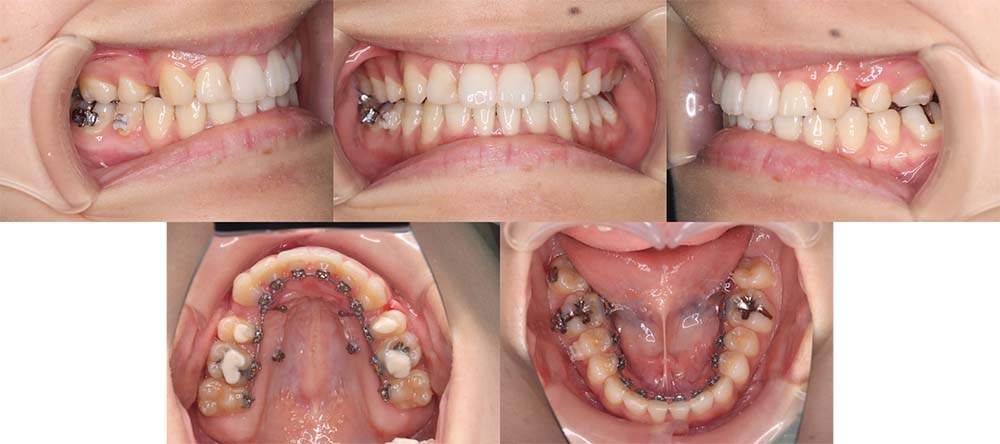

| 症例分類 | 上顎前突、口唇突出 |

| 診断名 | 骨格性上顎前突 |

| 主訴 | 口元が気になる、口が閉じられない、噛み合わせが悪い、発音に支障あり |

| 年齢 | 24歳10ヶ月 |

| 性別 | 女性 |

| 抜歯部位 | 上の左右第一小臼歯と下の左右第二小臼歯(4本) |

| 使用装置 | 上は裏側、下は表側のワイヤー装置 |

| 治療期間 | 2年11ヶ月 |

| 保定装置 | 固定式保定装置、取り外し式保定装置(8時間) |

| 費用 |

[検査・診断料] ¥49,500 [基本施術料] ¥1,056,000 [調整料] ¥5,500/回 [抜歯] ¥5,500/本 [保定装置] ¥55,000(税込) 抜歯や虫歯治療は他院にて費用が別途かかります。(抜歯¥4,000〜10,000/本)

上下前歯の唇側傾斜があり口唇閉鎖不全と口唇突出感があるため上顎両側の第一小臼歯と下顎両側の第二小臼歯を抜去して治療を行いました。

矯正用アンカースクリューを用いて前歯をしっかりと舌側移動させることができました。

歯の動きが遅かったため治療期間が予定より延びてはしまいましたが、口唇閉鎖不全と口唇突出感の改善をすることができました。